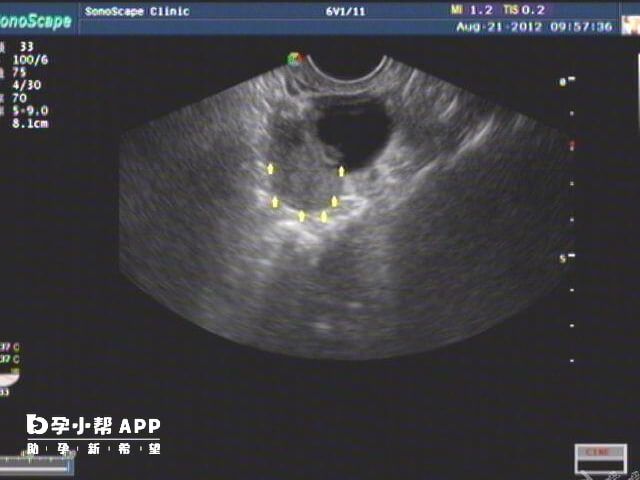

拮抗剂方案:主要用于卵巢高反应人群(如多囊卵巢综合征患者)。对于正常反应、低反应及首次试管婴儿失败的患者,医生可以根据患者的具体情况选择拮抗剂方案。